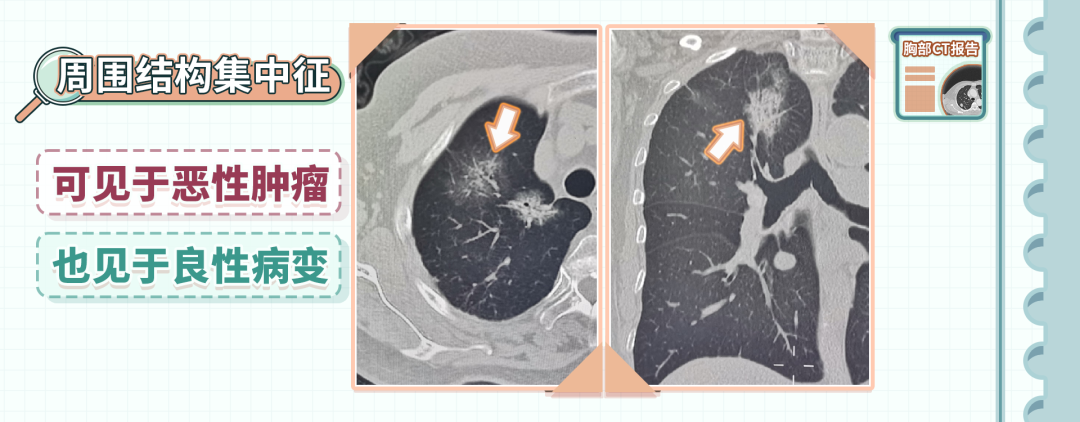

7、周围结构集中征

周围结构集中征是指结节周围的气管、支气管,以及邻近的动脉和静脉向结节聚拢,可以见于恶性肿瘤,也可以见于良性病变

但是当聚拢特别明显的时候,要高度警惕恶性的可能。